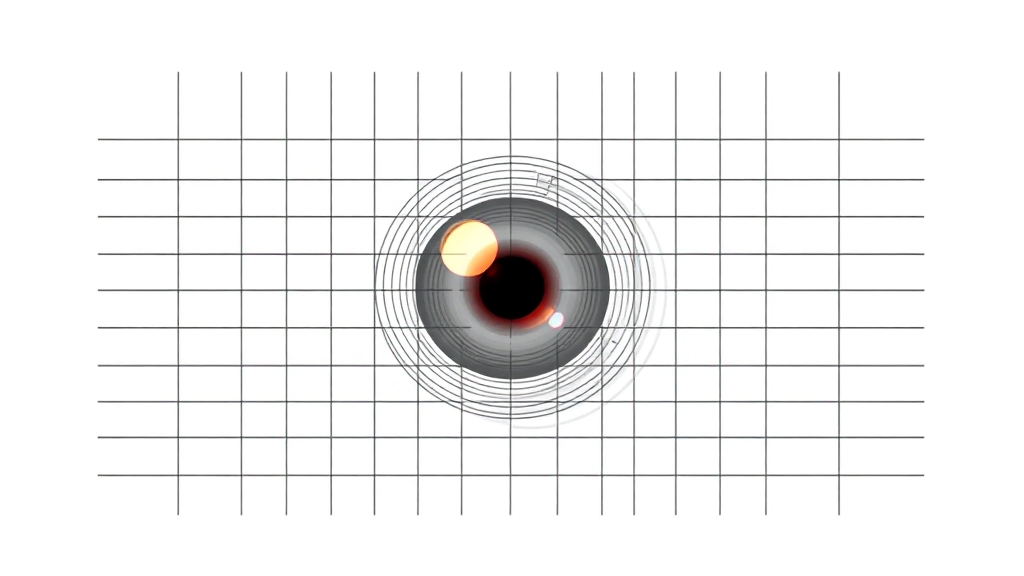

초기 증상이 있다면 자가진단을 통해 상태를 확인해 보세요. 암슬러 격자 검사가 유용합니다. 이 검사는 직선이 휘어져 보이는지 확인하는 데 도움을 줍니다.

암슬러 격자를 눈앞에 두고 한쪽 눈을 가린 채 검사합니다. 안경이나 렌즈를 착용한 상태에서 진행해야 정확합니다. 선이 흐릿하거나 끊어져 보이면 황반변성을 의심해야 합니다.

암슬러 격자는 자가진단 도구일 뿐 정확한 진단은 어렵습니다. 글자가 흔들려 보이거나 사물 중앙이 흐릿하면 안과 검사가 필요합니다. 안저 검사, 형광안저촬영 등으로 망막 상태를 정확히 파악할 수 있습니다. 40세 이상은 1년에 한 번 정기 검진을 받는 것이 좋습니다.

암슬러 격자 테스트는 집에서 간편하게 시력 변화를 확인하는 방법입니다. 50세 이상이거나 가족력이 있는 분들에게 중요합니다.

밝은 조명 아래에서 안경이나 렌즈를 착용한 상태로 테스트합니다. 한쪽 눈을 가린 후, 중앙의 검은 점에 집중하면서 주변 격자 선을 관찰합니다.

선이 굴곡지거나 물결 모양으로 보이면 황반변성을 의심할 수 있습니다. 양쪽 눈을 번갈아 가며 테스트하세요.

격자를 눈에서 30~40cm 거리에 두고 한쪽 눈을 가린 후, 중앙의 점을 보면서 격자 선이 휘어지거나 흐릿하게 보이는지 확인합니다.